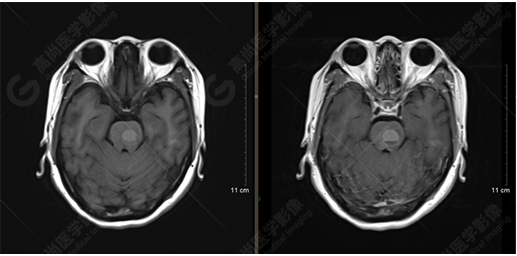

以下是MRI平掃及增強(qiáng)掃描:

T1WI及T1增強(qiáng)序列

橋腦見(jiàn)一類圓形異常信號(hào)影,直徑約1.3cm,呈T1WI稍高信號(hào),T2WI及FLAIR序列高信號(hào),其內(nèi)見(jiàn)高低信號(hào)分層,增強(qiáng)后無(wú)明顯強(qiáng)化。大腦鐮前部旁見(jiàn)兩個(gè)結(jié)節(jié)影,較大者直徑約1.4cm,呈各序列等信號(hào),增強(qiáng)后呈均勻明顯強(qiáng)化,鄰近大腦鐮增厚、強(qiáng)化。右側(cè)額葉腦白質(zhì)內(nèi)見(jiàn)一斑點(diǎn)狀等T1長(zhǎng)T2信號(hào)影,F(xiàn)LAIR序列呈高信號(hào),增強(qiáng)后無(wú)強(qiáng)化;余腦實(shí)質(zhì)內(nèi)未見(jiàn)局灶性信號(hào)異常,增強(qiáng)后未見(jiàn)異常強(qiáng)化。各腦室、腦池大小、形態(tài)均正常,中線結(jié)構(gòu)居中,幕下小腦無(wú)異常。矢狀面示垂體大小形態(tài)正常,未見(jiàn)局灶性信號(hào)異常。